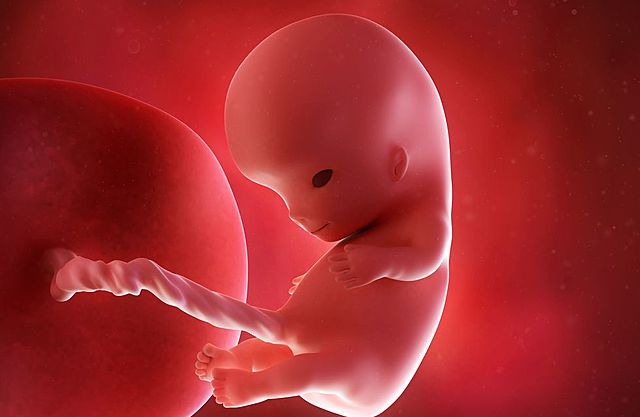

Embriogenesis

Proceso que se inicia tras la fecundación de los gametos para dar lugar al embrión, en las primeras fases del desarrolo de los seres pluricelulares.

• Formación y sexo del feto

Formación y sexo del feto

En el 3er mes ya está formador los órganos reproductivos y se puede observar que sexo del infante.